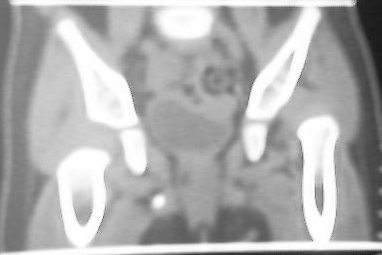

应该是典型的先髋。蛙式复位就可以了,何必ct呢。

先天性左侧髋关节脱位。

左侧先天性髋关节脱位.典型!